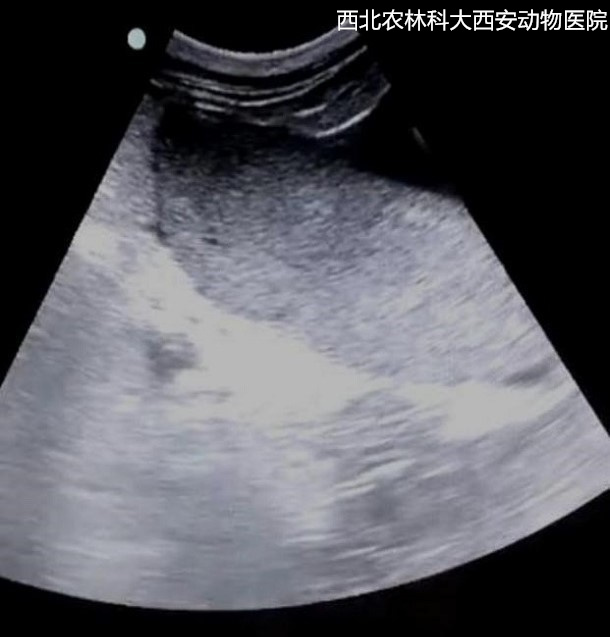

輔助檢查:腹部平片顯示腹腔有一中等密度占位性病變位于左下腹部,腹部器官邊緣銳利程度消失,腹部影像漿膜細節(jié)不能清晰可見,胃和部分腸管積氣,提示腹腔積液、疑似占位待查見(圖1)。為進一步診斷腹部占位的性質,對患寵進行了超聲檢查,結果顯示腹腔間隙無回聲,腸管游離,腹腔肝后至膀胱有一非均質、低回聲腫物,邊緣圓鈍,輪廓清晰,腫物內部偶見低回聲病灶。提示腹腔積液、脾腫大且結構異常,未見扭轉,待查見(圖2)。

圖二